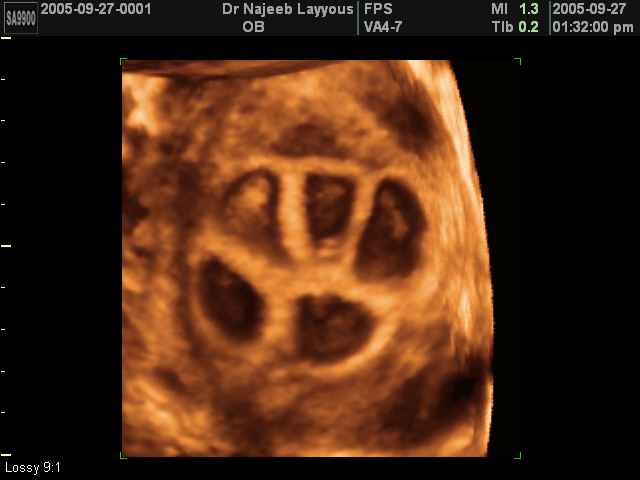

صور لتوائم بجهاز الالتراساوند ثلاثي الأبعاد | الدكتور نجيب ليوس

صور لتوائم بجهاز الموجات فوق صوتية ثلاثي الأبعاد